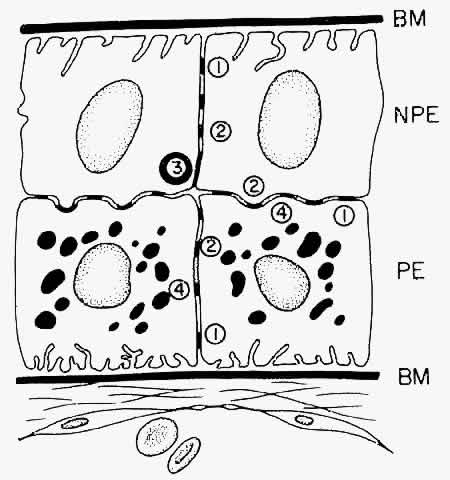

NONPIGMENTED CILIARY EPITHELIUM The ciliary epithelium consists of two layers: an inner nonpigmented (NPE) and

an outer pigmented layer (PE). These two layers derive from infolding

of the single cell layer of the optic vesicle against itself, to

form the optic cup. The potential space left between the two ciliary

layers rarely opens, owing to the frequency of junctional complexes

uniting the cells. A peculiar result of the infolding affects nomenclature

in this region, since the apices of the epithelial cells now face

each other across the potential space (Fig. 11). The bases of the cells face outward, toward the ciliary body stroma

for the PE, and toward the posterior chamber for the NPE. Basement membrane

covers the bases of both cell layers as is characteristic of epithelial

cells.  Fig. 11. Diagram showing the relationship of the two layers of ciliary epithelium. Basement

membrane (BM) covers their bases and their apices face each

other across a potential space. The cells are united by several types

of junctional complexes: 1, desmosomes; 2, gap junctions; and 4, puncta

adherentes. Onlythe apices of the nonpigmented epithelial cells (NPE) are

joined by “tight” junctions (3), composed of a zonula

occludens usually combined with a zonular adherens complex. PE, pigmented

epithelium. Fig. 11. Diagram showing the relationship of the two layers of ciliary epithelium. Basement

membrane (BM) covers their bases and their apices face each

other across a potential space. The cells are united by several types

of junctional complexes: 1, desmosomes; 2, gap junctions; and 4, puncta

adherentes. Onlythe apices of the nonpigmented epithelial cells (NPE) are

joined by “tight” junctions (3), composed of a zonula

occludens usually combined with a zonular adherens complex. PE, pigmented

epithelium.

There are a large number of intercellular junctions between the ciliary

epithelial cells, each giving important data about the specific functions

of these cells (see Fig. 11). Toward the base of the NPE cells their lateral sides are joined by desmosomes (see Fig. 15). At their apical ends they are connected by typical tight junctional